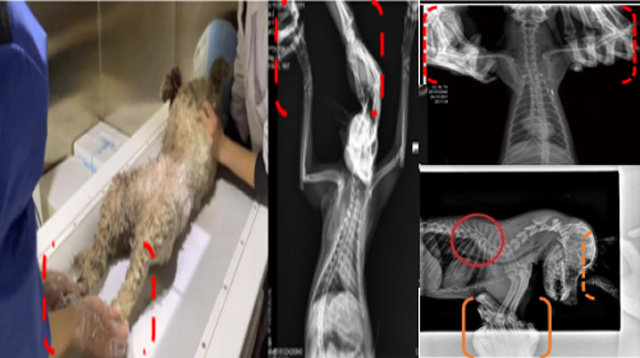

現在寵物醫療設備得到高速發展,現在有越來越多的寵物診療機構配置X射線裝置如寵物DR。寵物骨折或者有其他疾病不能通過直觀看出來的。寵物診所醫生都會使用寵物DR來做輔助檢查。但是有時候寵物醫生沒有加強防護,就在寵物DR室給寵物拍X片做檢查。這樣也是會受到X射線的輻射。因為X射線上崗是屬于職業病危害崗位。長期的輻射會對人體造成一定的危害。寵物醫生也需要接受X射線照射的上崗前都必須進行放射工作人員的職業健康體檢。體檢不合格的話是不能擔任放射工作的。未經上崗前職業健康體檢的勞動者從事接觸職業病危害作業的行為,已經違反了《中華人民共和國職業病防治法》第三十五條規定,依據《中華人民共和國職業病防治法》第七十五條規定,需要進行整改罰款。開展寵物放射診療活動,在日常工作中,對本機構的X射線危害的職業病防治,需要知道并做到以下內容: